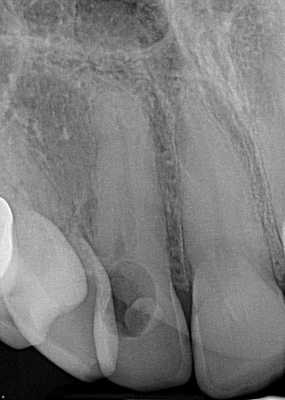

Фото 1. Рентгенограмма, демонстрирующая пример внутренней резорбции корня.

Фото 2. Рентгенограмма, демонстрирующая пример внешней воспалительной резорбции корня.

Фото 3. Рентгенограмма, демонстрирующая пример резорбции по причине давления.

Фото 4. Рентгенограмма, демонстрирующая пример инвазивной пришеечной резорбции.

Фото 8. Подтверждение диагноза ИПКР на рентгенограмме.